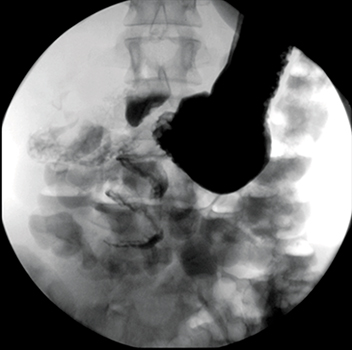

Paciente de sexo femenino, de 18 años, que concurre al servicio de emergencias presentando dolor epigástrico agudo e intermitente de 6 horas de evolución. Semiológicamente el dolor empeora con la ingesta y se asocia con náuseas y vómitos de tipo biliosos. Al examen físico, llama la atención la marcada distensión abdominal. Se solicitan como estudios complementarios una ecografía abdominal (Figura 1), un tránsito de intestino delgado con contraste hidrosoluble (Figura 2) y una tomografía computada con contraste oral y endovenoso (Figura 3).